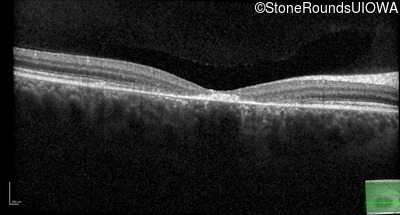

Optical Coherence Tomography - Right - 10/125 -1

Exemplar / OCT Stack